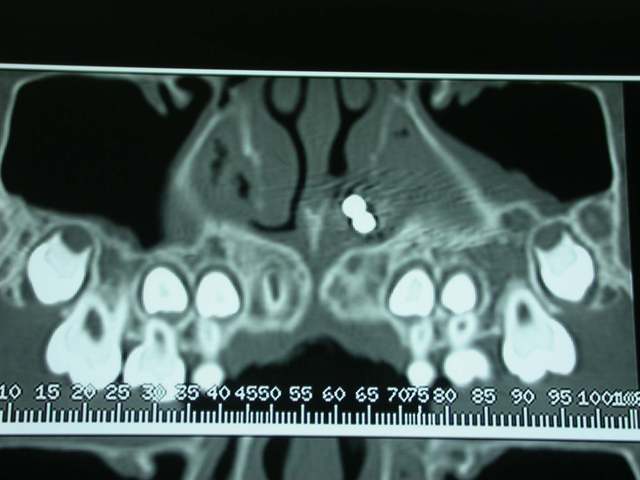

Je décide donc de faire réaliser un scanner et là c’est nouveau pour vous.

Une fois le scanner réalisé, je vois bien qu’il s’agit d’un objet composé de boules et l’adresse illico à son orl. Il la reçoit dans la foulée, et au vu du scanner, se refuse d’intervenir de peur de renvoyer plus loin l’objet. A son tour, il l’adresse à un hopital spécialisé enfants (Robert Debré). Au service ORL, ils tentent de retirer l’objet avec une pince (comme Dr House le faisait dans un épisode) et rien de neuf, aucune progression.

l'objet: une petite chainette boule métallique (celles qui sont accrochées à certains vetements et qu'on retrouve sur les bouchons de baignoire) complétement oxydée (noir de chez noir, avec diminution du diametre de certaines boules) .

temps de séjour estimé dans les fn: 4-5 ans